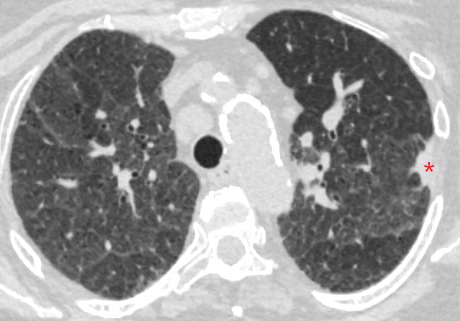

Ramsy Abdelghani, MD@Rabdelgh·

Growing LUL pleural based lesion with no airway leading to it and negative on IR biopsy. Was able to navigate close (within 2cm) to the lesion, biopsy, and adjust using CBCT. Positive for poorly differentiated carcinoma. I would have never tried this without CBCT and Robotics.